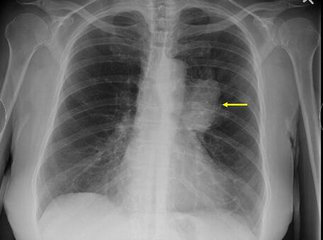

影像检查胸部X线检查可以了解肺癌的部位和大小,可看到由于支气管阻塞引起的局部肺气肿、肺不张或病灶邻近部位的浸润性病变或肺部炎变。

中央型肺癌